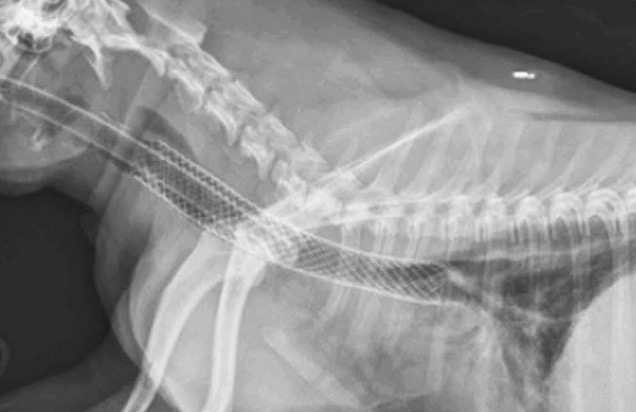

L’intervention est mini-invasive. Cela signifie que nous ne réalisons pas d’approche chirurgicale lourde. Tout se passe sous contrôle endoscopique ou radioscopique.

- Réalisation de vues radiologiques en inspiration et expiration

- Pose du stent

- Vérification de la pose